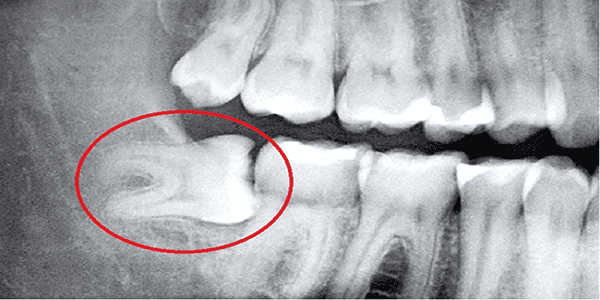

- Răng khôn gần dây thần kinh: Cần sử dụng máy chụp CT Cone Beam 3D để xác định chính xác vị trí, tránh tổn thương, do đó chi phí sẽ cao hơn.

- Khám Tổng quát và Chụp Phim X-quang/CT Cone Beam: Đánh giá chính xác vị trí, độ sâu, và mối liên hệ với dây thần kinh.

- Tổn thương Dây thần kinh: Thiếu máy móc chẩn đoán chính xác (như CT Cone Beam) và tay nghề bác sĩ non kém có thể gây tổn thương dây thần kinh vĩnh viễn.

- Trang thiết bị hiện đại: Bắt buộc phải có máy chụp phim chẩn đoán chính xác.